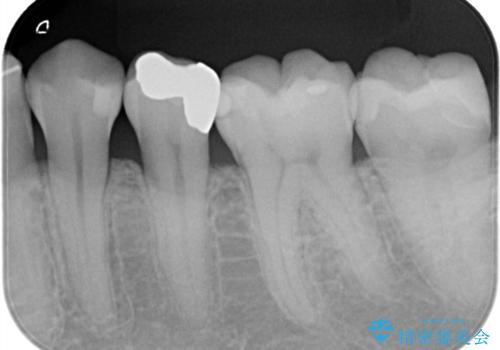

- 主訴:下の歯に入っている銀歯が笑うと目立つので白くしたい。

下顎臼歯部に入っている保険適用のメタルインレー(4箇所)を、審美性・適合性・清掃性の良いセラミックインレーにてやり替えました。